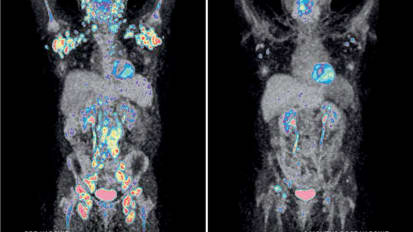

Learn more about advances in Nuclear Medicine and hear the amazing story of a patient treated at Mount Sinai’s Tisch Cancer Center.

Cancer Immunotherapy at Mount Sinai: Progress Towards Curing the Uncurable

Mount Sinai is moving the bar on immunotherapy to improve outcomes for patients